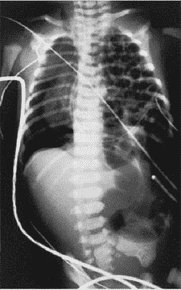

65) A full-term male newborn experiences respiratory distress immediately after birth. A prenatal sonogram was read as normal. An emergency radiograph is shown here. The patient is intubated and placed on 100% O2. Arterial blood gases reveal pH 7.24, PO2 60 kPa, and PCO2 52 kPa. The baby has sternal retractions and a scaphoid abdomen. Which of the following should be performed in the management of this patient?

Administration of intravenous steroids

Placement of bilateral tube thoracostomies

Immediate thoracotomy with lung resection

Immediate laparotomy with repair of the diaphragm

Mechanical ventilation with low tidal volumes